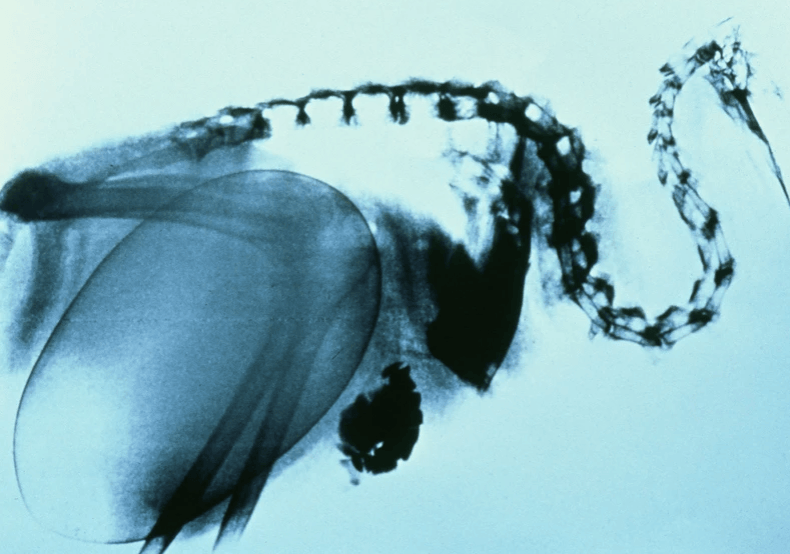

科学家们第一次知道这个事实的时候,根本不敢相信,这么大的鸟蛋是怎么在几维鸟的体内诞生出来的?难道不会挤压到它们的内脏器官吗?

终于在科技发展后,科学家们通过X光片知道了几维鸟蛋在成鸟体内的样子。根据X光片可以看到,这个鸟蛋会对几维鸟的肺部、气囊以及消化道造成巨大的压力,使它呼吸困难!甚至到了孕晚期,雌性几维鸟的卵会压得它们根本无法进食!它们会撑开腿走路,走一会儿就得休息一会儿。

卵形成到产下需要3~4周的时间,有时候甚至能一窝产下两枚卵!真的是难以想象,就像是人类女性生下了4~5岁的孩子。